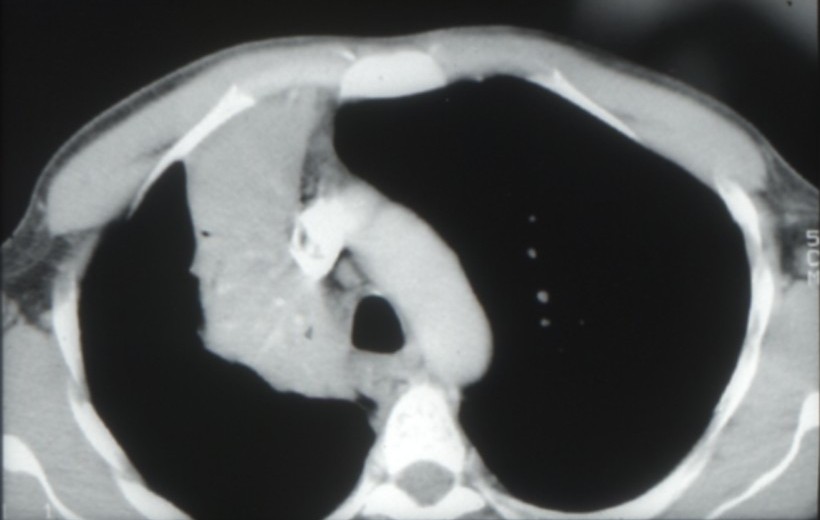

Cancers bronchiques